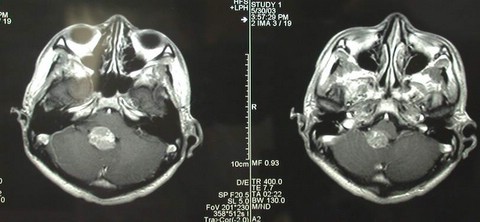

行显微手术治疗。全切肿瘤。术后图片如下: